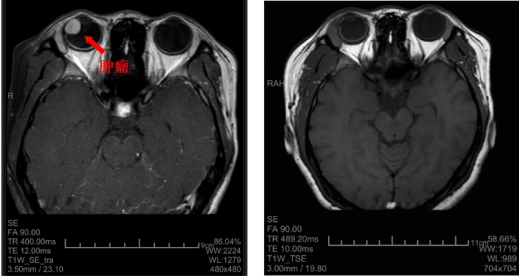

孙大卫在裂隙灯显微镜下发现晓琳的右眼内有一肿瘤,散瞳后肉眼可见瘤体。进一步检查发现,肿瘤位于患者右眼颞侧12点至6点钟位,纵径接近180度,从晶状体蔓延到眼底赤道部,横径超过15mm(而正常人的眼球直径约23mm),肿瘤在眼内脉络膜生长,瘤体向眼球内突出,高度约12mm。综合测量评估后专家认为肿瘤占据眼内体积的一半以上,且肿瘤生长速度较快,已经造成患者视物的遮挡,并逐渐出现肿瘤相关的眼内并发症,渗出性视网膜脱离,继发性白内障等,病情仍有进一步恶化的可能,建议手术治疗。

术前和术后的核磁影像学检查结果比较